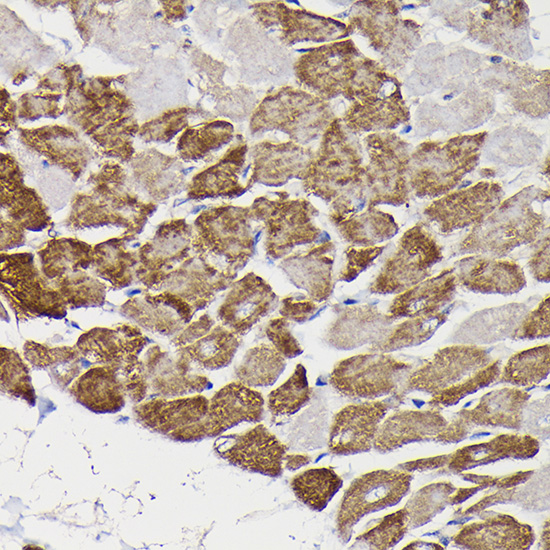

Immunohistochemistry of paraffin-embedded rat liver using Monoamine Oxidase B Rabbit pAb at dilution of 1:150 .Perform high pressure antigen retrieval with 10 mM citrate buffer pH 6.0 before commencing with IHC staining protocol. -